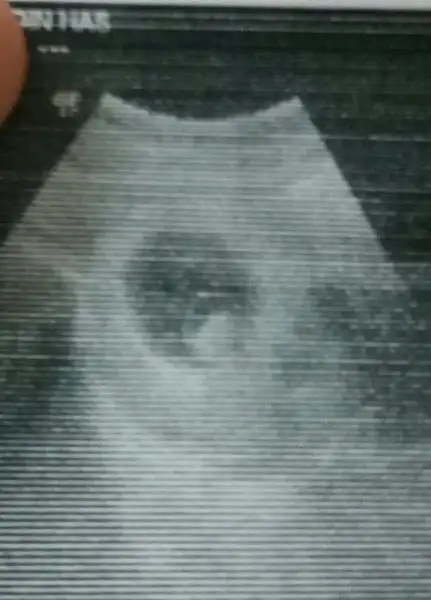

Burda 6 -4 haftalık ne tarafa daha yakın gözüküyo acaba

• 1488541259129-1079750514.webp

1488541259129-1079750514.webp

8,6 KB · Görüntüleme: 117